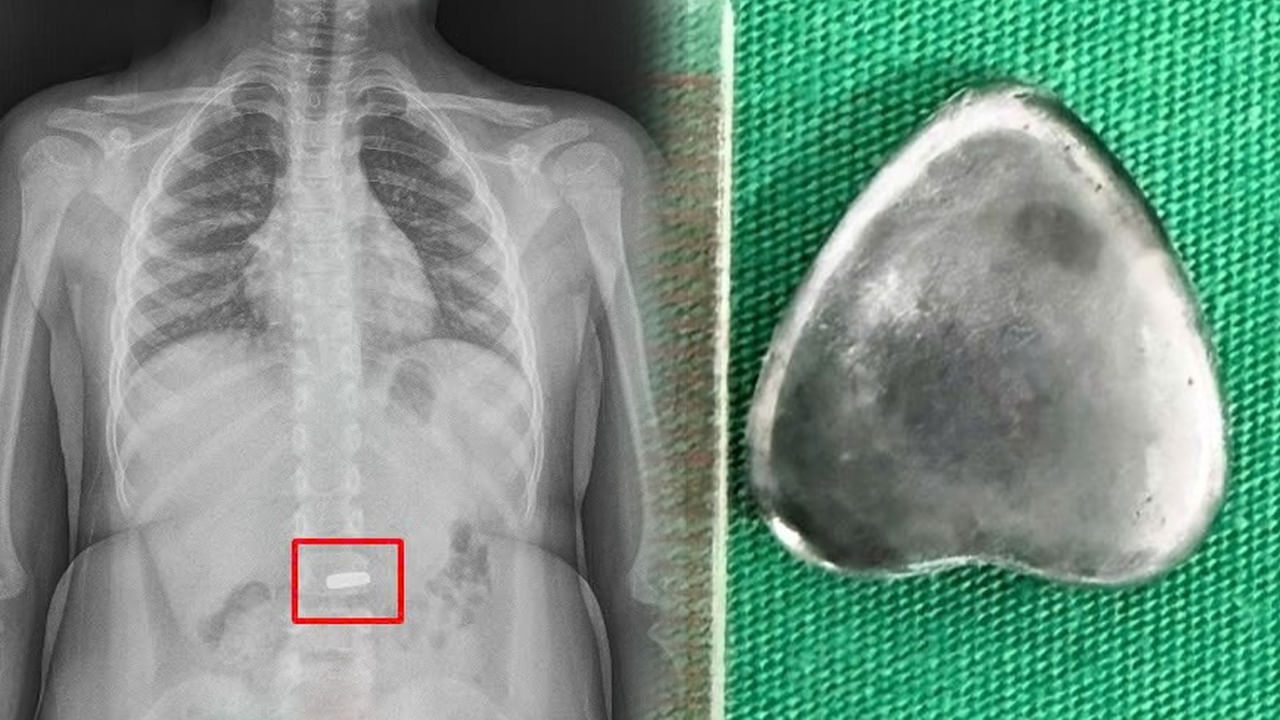

ఓ విచిత్ర కేసు వియత్నాంలో చోటు చేసుకుంది. ఆరేళ్ల బాలుడి కడుపు నుంచి గుండె ఆకారంలో ఉన్న అయస్కాంతాన్ని తొలగించారు వైద్యులు. భోజనం తర్వాత ఆడుకుంటుండగా ఆ బాలుడు ప్రమాదవశాత్తు 2 సెంటీమీటర్ల పొడవున్న ఆయస్కాంతాన్ని మింగేశాడు. అదృష్టవశాత్తూ ఆ బాలుడు అయస్కాంతాన్ని మింగడం.. అతడి తల్లిదండ్రులు చూడటంతో వెంటనే సమీపంలోని ఆస్పత్రికి తీసుకెళ్లారు. వైద్యులు ఎక్స్రే తీయగా.. అది సరిగ్గా రోగి పేగుల్లో ఇరుక్కున్నట్టు గమనించారు. అది పేగుల్లో చిల్లులు, నెక్రోసిస్కు కారణమయ్యే ఛాన్స్ ఉండటంతో.. వెంటనే ఎండోస్కోపీ ద్వారా ఆయస్కాంతాన్ని తొలగించారు. వియత్నాంలోని విన్లాంగ్లో ఉన్న జుయెన్ జనరల్ హాస్పిటల్లోని వైద్య బృందం ఈ శస్త్రచికిత్సను విజయవంతంగా చేశారు.

బాలుడికి ఎలాంటి గాయాలు కాకుండా చూసుకున్నారు. ఆపరేషన్ అనంతరం ఆ సాయంత్రమే అతడ్ని డిశ్చార్జ్ చేశారని తెలుస్తోంది. అక్కడ పని చేసే డాక్టర్ మాట్లాడుతూ.. ‘రోగిని త్వరగా ఆసుపత్రికి తీసుకువచ్చారు. కాబట్టి తొందరగా ఆపరేట్ చేయగలిగాం. ఆ వస్తువు పదునైనది కాకపోవడం వల్ల శరీరంలో ఎలాంటి గాయాలు కాలేదు. రక్తస్రావం కూడా జరగలేదు. ఒకవేళ ఎక్కువసేపు ఆ వస్తువు లోపలే ఉన్నట్లయితే.. జీర్ణవ్యవస్థకు కూడా తీవ్ర నష్టం వాటిల్లే ఛాన్స్ ఉంది.’ అని అన్నారు.